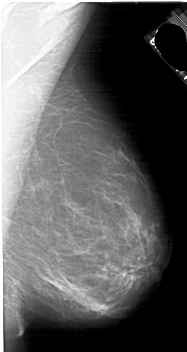

A_1880_1.RIGHT_CC

RIGHT_MLO LINES 4921 PIXELS_PER_LINE 2611 BITS_PER_PIXEL 12 RESOLUTION 43.5 NON_OVERLAY